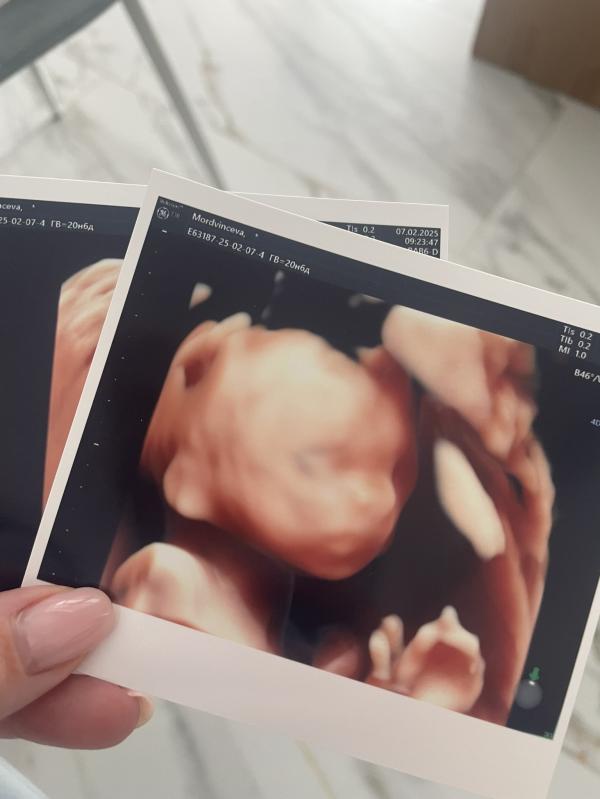

Я помню, что еще после первого теста чувствовала, что будет двойня. На первых УЗИ и правда нам показали двух крошечных человечков. Все что было дальше, хоть и были милые и чудесные моменты, я вспоминаю с трудом, потому что все это затмила моя госпитализация на сохранение на 21 неделе беременности.

На 20 неделе мы узнали, что будет два мальчика, хотя снились мне мальчик и девочка.